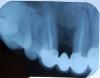

igorpol Опубликовано 19 июля, 2009 Поделиться Опубликовано 19 июля, 2009 Пару недель назад при надавливании на коронку стал чувствовать небольшой дискомфорт, не болезненный (тройка). Впереди стоит металлокерамика. Врач прописал нимесил 4 дня и траумель 3 дня. Нимесил пропил, перед уколами сделали снимок, сказали что скорее всего воспаление в корне, есть два варианта, либо снимать коронку (это мост т.е. сразу три зуба) либо операцию (разрез) кажется резекция. Так не хочется ни того ни другого. Неужели нельзя снять воспаление просто уколами? Снимки прикрепляю. Ссылка на комментарий

stomal Опубликовано 20 июля, 2009 Поделиться Опубликовано 20 июля, 2009 На мой взгляд на первом снимке имеется косой перелом корня опорного зуба , и боли скорее всего от него. Поправте доктора если я не прав. Ссылка на комментарий

Zlata-doctor Опубликовано 20 июля, 2009 Поделиться Опубликовано 20 июля, 2009 На мой взгляд на первом снимке имеется косой перелом корня опорного зуба , и боли скорее всего от него. Поправте доктора если я не прав. Перелома не вижу, а вот эндодонтическое лечение не на высоте (переапикальная инфекция). Показан не разрез и не антибиотики, а повторное эндолечение данного зуба Ссылка на комментарий

stomal Опубликовано 20 июля, 2009 Поделиться Опубликовано 20 июля, 2009 Перелома не вижу, а вот эндодонтическое лечение не на высоте (переапикальная инфекция). Показан не разрез и не антибиотики, а повторное эндолечение данного зубаНа ваш взгляд эта косая линия просто наложение? То что эндо не на высоте понятно . Ссылка на комментарий